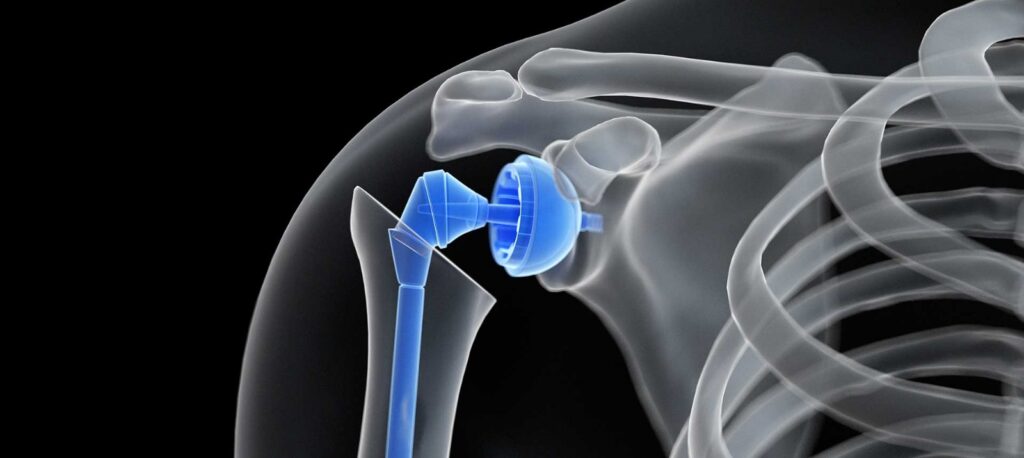

Omuz protezi, omuz eklemindeki ağrı, hareket kısıtlılığı veya fonksiyon kaybı nedeniyle omuz ekleminin tamamen veya kısmen değiştirilmesi amacıyla yapılan cerrahi bir müdahaledir. Genellikle osteoartrit, romatoid artrit, omuz kırıkları veya omuz eklemindeki deformasyonlar gibi durumlardan kaynaklanan şiddetli ağrı ve fonksiyon kaybı yaşayan bireylerde tercih edilir. Omuz protezi cerrahisinde, omuz eklemindeki hasarlı kısımlar çıkarılır ve yerine metal, plastik veya seramik bileşenler yerleştirilir. Bu ameliyatın birkaç türü vardır; tam omuz protezi, yalnızca omuz başının değiştirilmesiyle yapılan kısmi omuz protezi ve rotator manşet fonksiyonunun kaybedildiği durumlarda kullanılan ters omuz protezi bunlar arasında yer alır. Ameliyat öncesinde hastanın sağlık durumu değerlendirilir ve cerrahi müdahale genellikle genel anestezi altında yapılır. Ameliyat sonrası hastalar birkaç gün hastanede kalır ve fiziksel terapi başlar. Fiziksel terapi, omuzun hareketliliğini artırmayı ve kasları güçlendirmeyi amaçlar. Omuz protezi sonrasında, genellikle 6-8 hafta içinde hastalar günlük aktivitelerini yapabilecek seviyeye gelirler. Protezlerin ömrü genellikle 15-20 yıl arasında değişir, ancak bu ömür, hastanın yaşı, aktivite seviyesi ve protez bakımı gibi faktörlere bağlı olarak farklılık gösterebilir. Omuz protezi, doğru hastalarda yaşam kalitesini önemli ölçüde artırabilir ve ağrısız bir yaşam sağlayabilir.